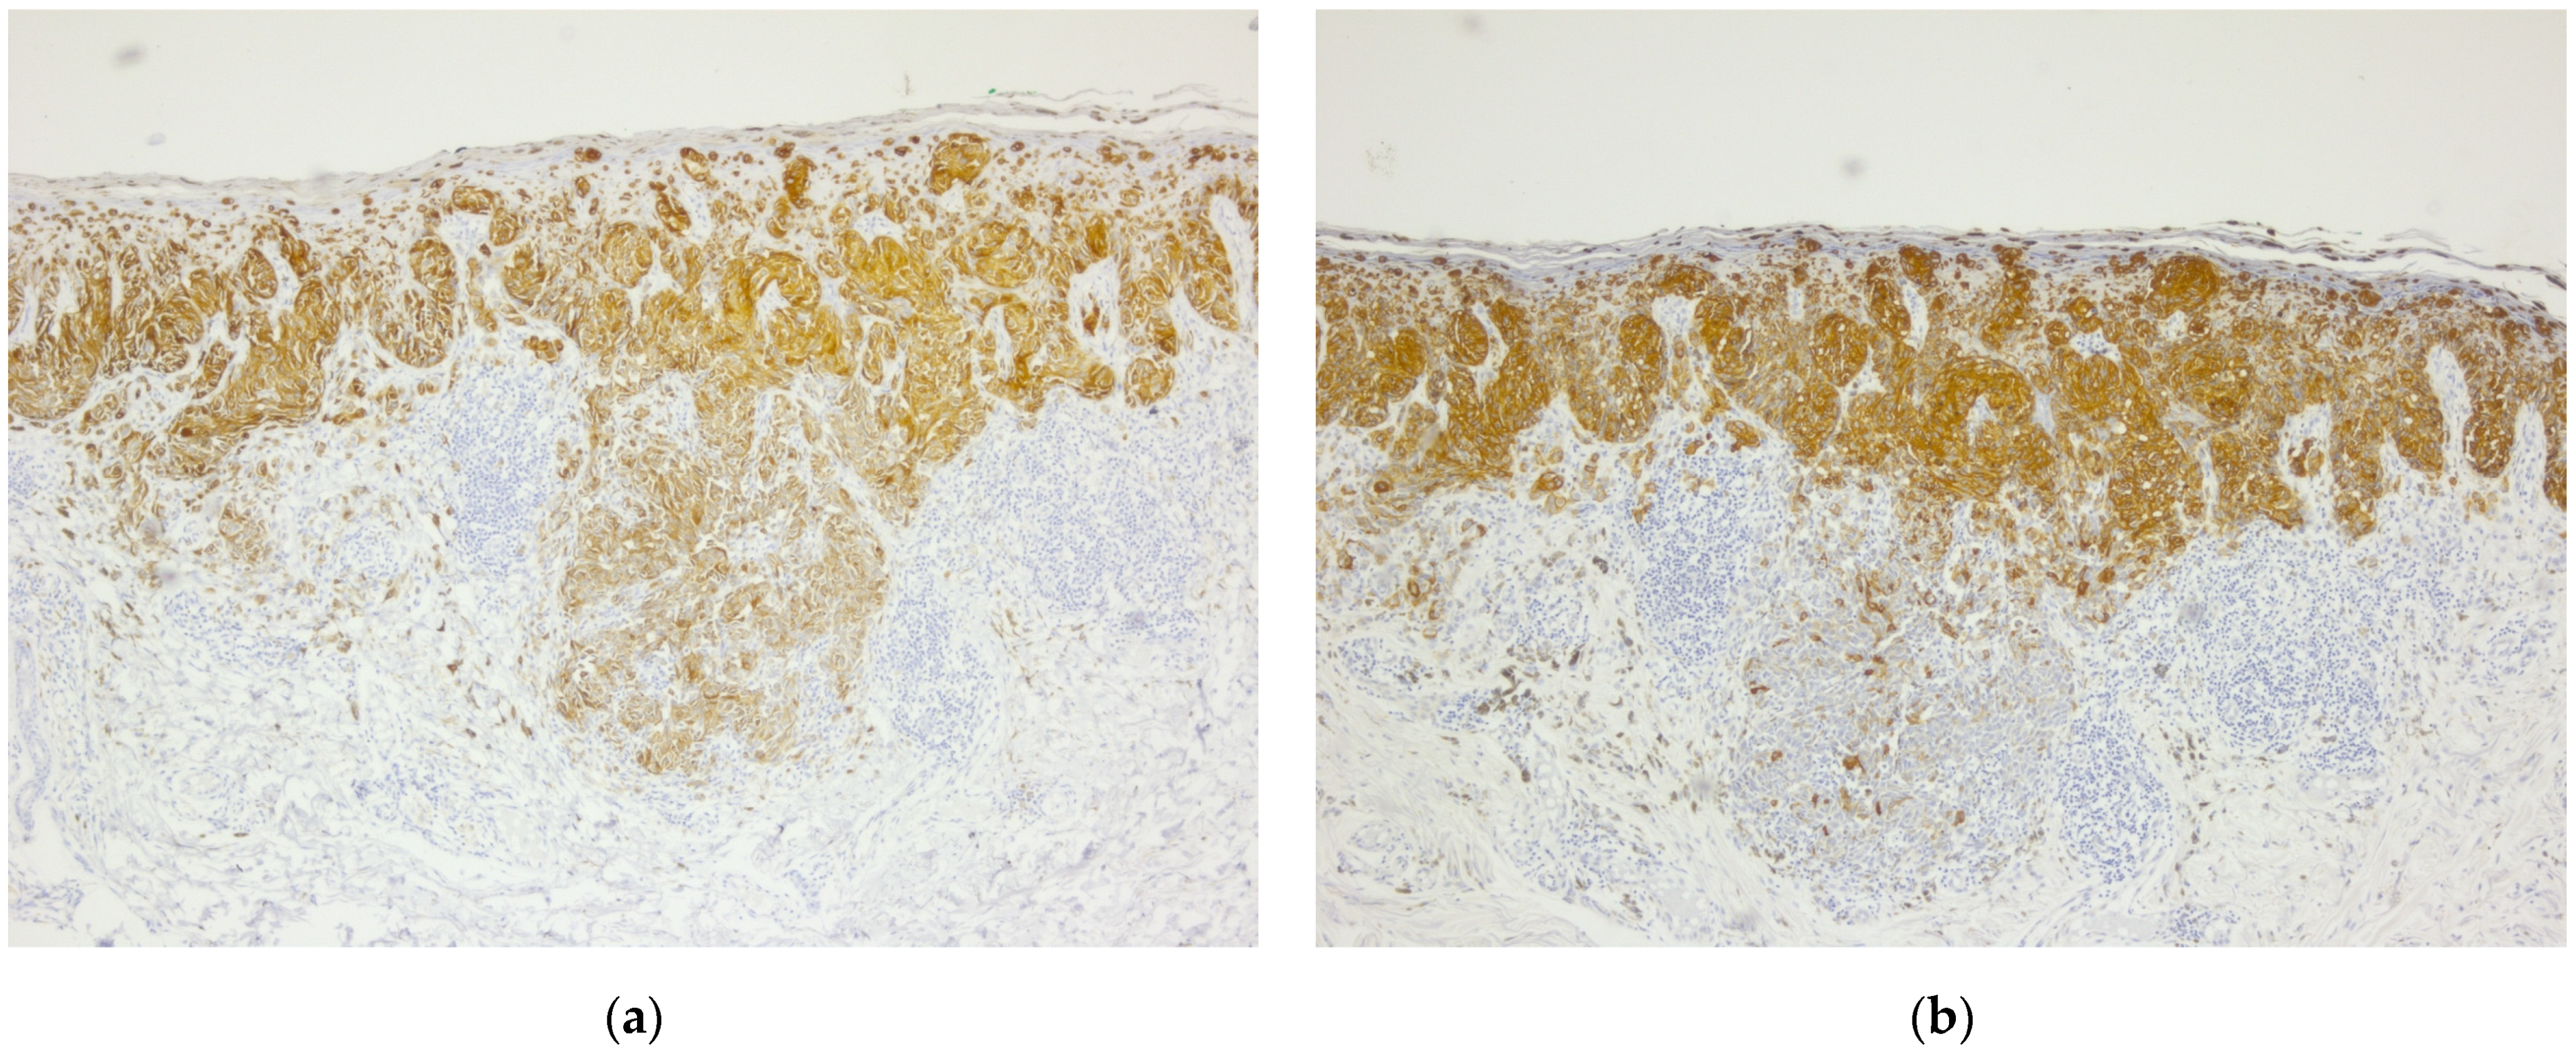

- Raspollini, M.R.; Nesi, G.; Baroni, G.; Girardi, L.R.; Taddei, G.L. Immunohistochemistry in the Differential Diagnosis Between Primary and Secondary Intestinal Adenocarcinoma of the Urinary Bladder. Appl. Immunohistochem. Mol. Morphol. 2005, 13, 358–362. [Google Scholar] [CrossRef]